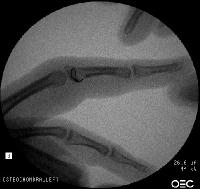

Xrays show an apparently healed PIP fracture dislocation with dorsal subluxation - but concentric tracking of the abnormal palmar articulation.